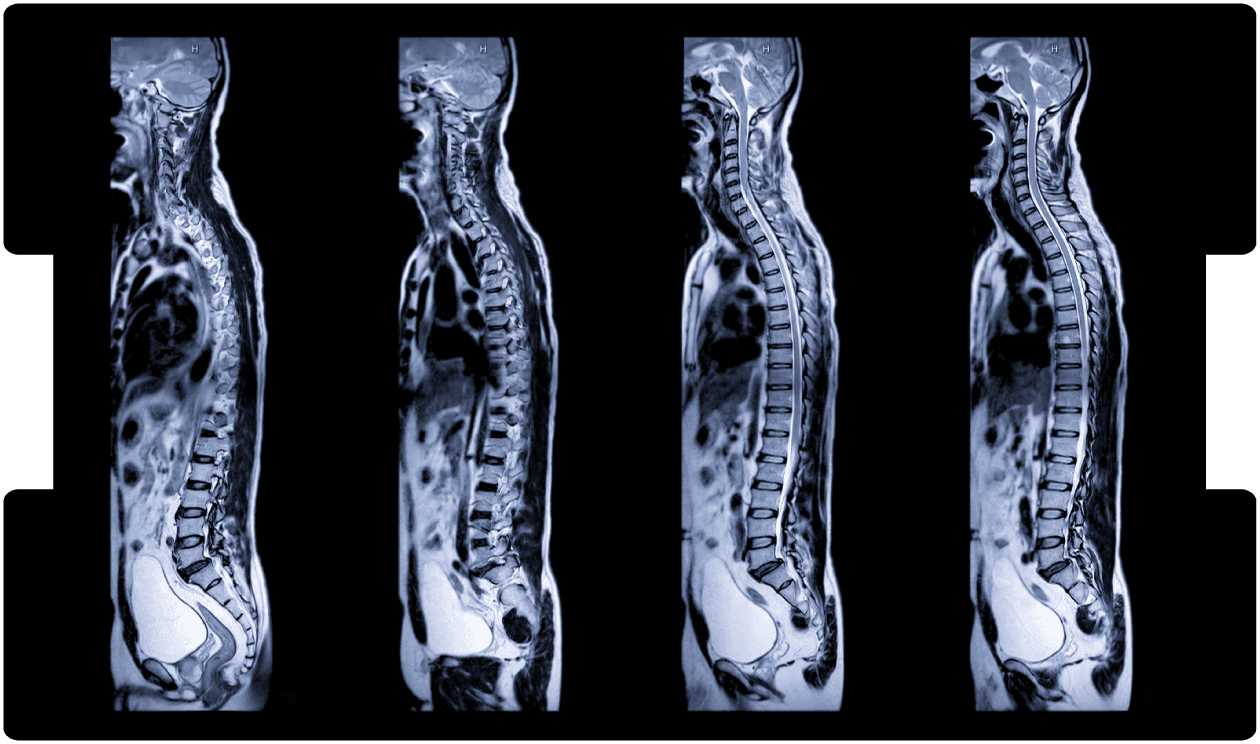

Cauda Equina Diagnosis: Clinical Failures and Claim Implications

By Poorna Veerappa, Advanced Spinal Physiotherapist & Expert Witness